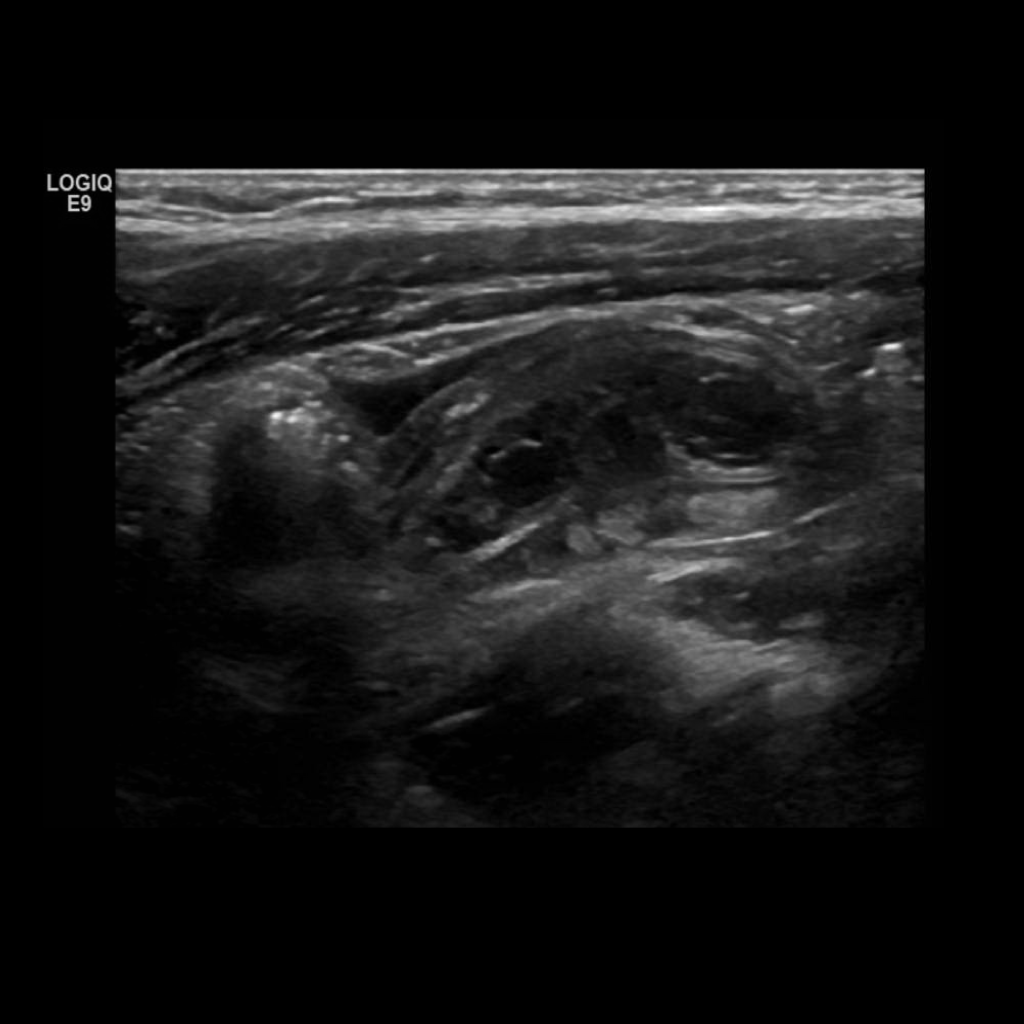

Appendicitis 9

Hyperemic appendix with loss of gut signature and free fluid, perforated appendicitis.